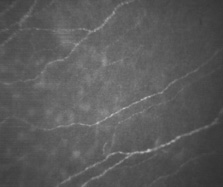

endothelium. Exp Eye Res 23:285, 1976 94. Amann J, Holley GP, Lee SB, et al: Increased endothelial cell density in the paracentral and peripheral regions

of the human cornea. Am J Ophthalmol 135:584, 2003 95. Bourne WM, Nelson LR, Hodge DO: Central corneal endothelial cell changes over a ten-year period. Invest Ophthalmol Vis Sci 38:779, 1997 96. Gallagher B: Primary cilia of the corneal endothelium. Am J Anat 159:475, 1980 97. Senoo T, Obara Y, Joyce N: EDTA. a promoter of proliferation in human corneal endothelium. Invest Ophthal Vis Sci 41:2930, 2000 98. Senoo T, Joyce NC: Cell cycle kinetics in corneal endothelium from old and young donors. Invest Ophthal Vis Sci 41:660, 2000 99. Joyce N: Proliferative capacity of the corneal endothelium. Prog Retin Eye Res 22:359, 2003 100. Sherrard ES, Ng YL: The other side of the corneal endothelium. Cornea 9:48, 1990 101. Rae JL, Watsky MA: Ionic channels in corneal endothelium. Am J Physiology 270:975, 1996 102. Rozsa AJ, Beuerman RW: Density and organization of free nerve endings in the corneal epithelium